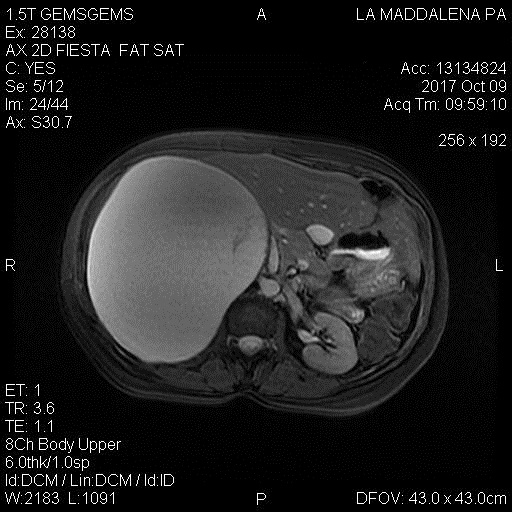

La donna aveva scoperto la neoplasia già in fase di gravidanza, a seguito di alcuni controlli effettuati in un’altra struttura sanitaria del capoluogo. Dopo l’iniziale drenaggio percutaneo per ridurre il volume della massa, e favorire il parto, si era inizialmente sperato in una definitiva risoluzione del quadro senza necessità di intervenire chirurgicamente. Sfortunatamente, qualche settimana dopo il parto, la massa si è ripresentata fino a raggiungere dimensioni enormi, tanto da determinare una vistosa compressione e dislocazione degli organi interni della paziente (tra questi il fegato ed il rene di destra) la quale accusava disturbi sempre più pesanti. Così, la donna ha deciso di rivolgersi alle cure de “La Maddalena”, dove, prima della prospettiva dell’intervento chirurgico, è stata sottoposta ad alcuni esami diagnostici per indagare sulla natura della massa.

“La paziente è arrivata con referto di sospetta neoformazione cistica gigante del lobo epatico di destra – spiega Lucio Mandalà, responsabile della Chirurgia epatobiliare, che ha eseguito l’intervento come primo operatore – , ciò si spiega in relazione ai rapporti che questa massa contraeva con la parte destra del fegato da non consentire ai radiologi una sicura diagnosi circa l’origine della neoplasia. L’indicazione all’intervento era determinata dalla grave sintomatologia accusata dalla paziente, dalla tendenza a recidivare se drenata e non ultimo dalla necessità di una diagnosi di natura. Così, dopo un consulto in equipe, abbiamo deciso di proporre alla giovane donna di provare ad intervenire in laparoscopia, ed evitare un’incisione che sarebbe stata devastante per la neomamma”.

“Il trattamento chirurgico con approccio mininvasivo di voluminose masse addominali, a prescindere dalla loro natura, – spiega il chirurgo – è spesso controindicato per insuperabili difficoltà tecniche. Tuttavia si deve sempre valutare questa possibilità per poter offrire i più elevati standard di cura che oggi risultano possibili grazie a tecnologie sempre più avanzate. Si è trattato di un intervento molto complesso durante il quale abbiamo scoperto che la componente solida da cui originava questa formazione era il surrene di destra e non il fegato; un organo, il surrene che nella norma ha dimensioni poco superiori ad una castagna e che nella donna non era più riconoscibile in quanto completamente sostituito dalla neoplasia cistica. Poco prima dell’intervento, – prosegue il chirurgo – è stato necessario aspirare una parte della componente liquida della massa in modo che la parziale riduzione di volume della stessa potesse consentire di procedere in laparoscopia, metodica che, si sa, richiede l’immissione nella cavità addominale di un gas inerte per creare lo spazio anatomico tra gli organi su cui intervenire. L’intervento è iniziato e si è concluso in laparoscopia, con rimozione completa della massa e senza praticare incisioni sulla paziente”. L’intervento, avvenuto nel mese di novembre 2017 ed è perfettamente riuscito. La paziente si è recentemente sottoposta ad un primo controllo ed è in buone condizioni di salute.